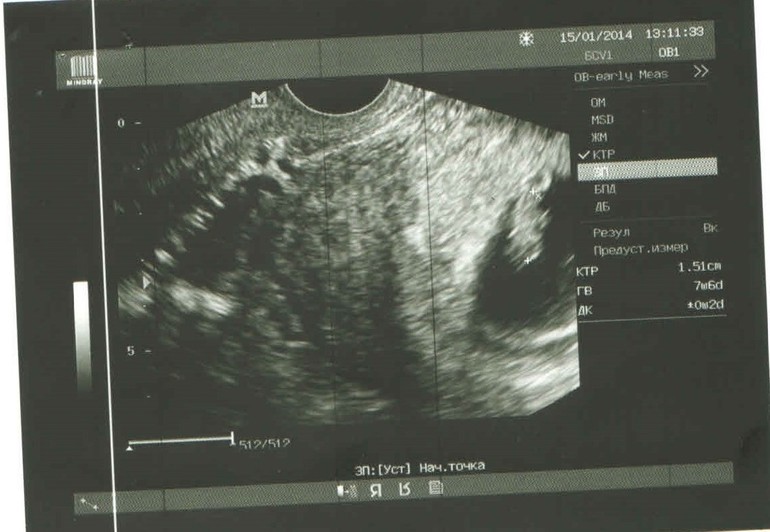

Перед тем, как встать на учет ко врачу, я сделала узи. Нашли 1 плодное яйцо, у эмбриончика СБ просматривалось. Срок 8 недель.

Участковый врач после осмотра на кресле сказала, что матка больше срока и скорее всего у меня там не один.

В ближайшие дни нет возможности посетить узиста - нахожусь в командировке, а муж на снимке "разглядел" еще одного.

Посмотрите, если не трудно, и напишите свое мнение.